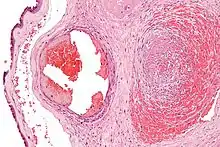

La fibrine ne préexiste pas dans le sang ; elle n'apparaît qu'au moment de la coagulation. La coagulation est la transformation du fibrinogène (soluble) par la thrombine en fibrine insoluble qui conduit à la formation d'un caillot. Dans un caillot, la fibrine forme un maillage qui emprisonne les cellules sanguines.